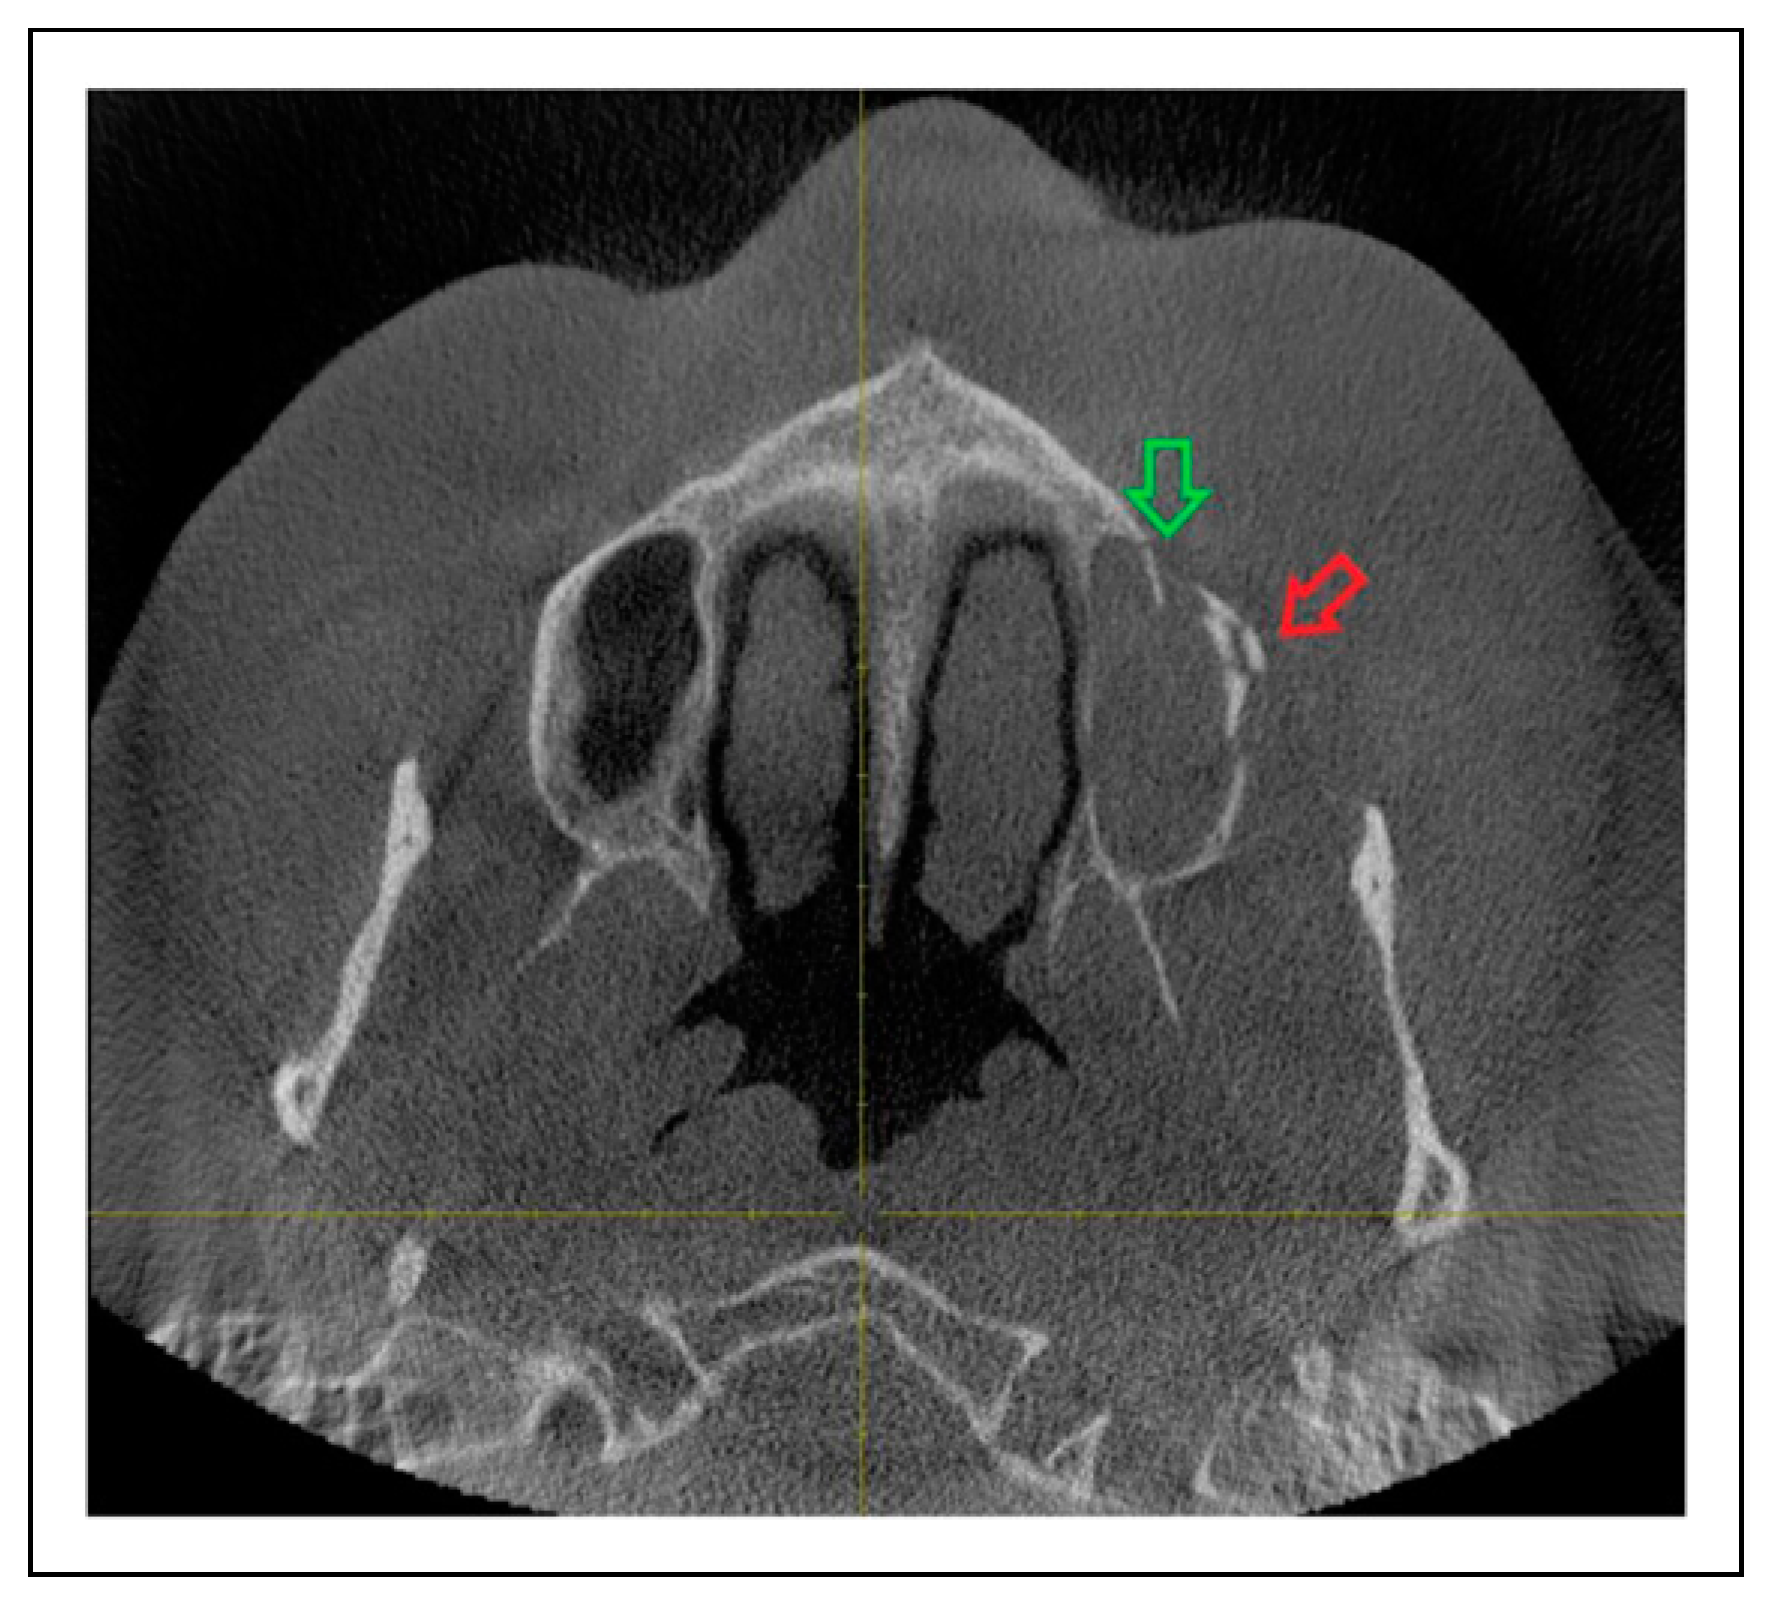

- Fracture location according to the anatomic sutures of the zygoma

- Radiologic involvement of maxillary sinus wall and paranasal buttress fractures.

Patterns of ZMO Fractures Regarding the Anatomic Sutures of the Zygoma

- Unisutural fracture (isolated fracture of a single anatomic suture of the zygoma):

- Zygomaticomaxillary suture (ZM)

- Infraorbital rim (IOR)

- Complete ZMO fracture involving all 5 anatomic sutures of the zygoma:

- ZM suture + IOR + ZF suture + ZS suture + ZT

Fracture Prevalence of Maxillary Sinus Wall and Paranasal Buttress as Concomitance to the ZMO